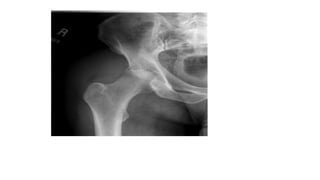

Rheumatoid arthritis

Early radiographic changes : soft tissue swelling and periarticular demineralization.

Later changes: include uniform loss of joint space and bony erosions

Advanced changes: include diffuse bony erosions, joint subluxation, and

foreshortening of digits.